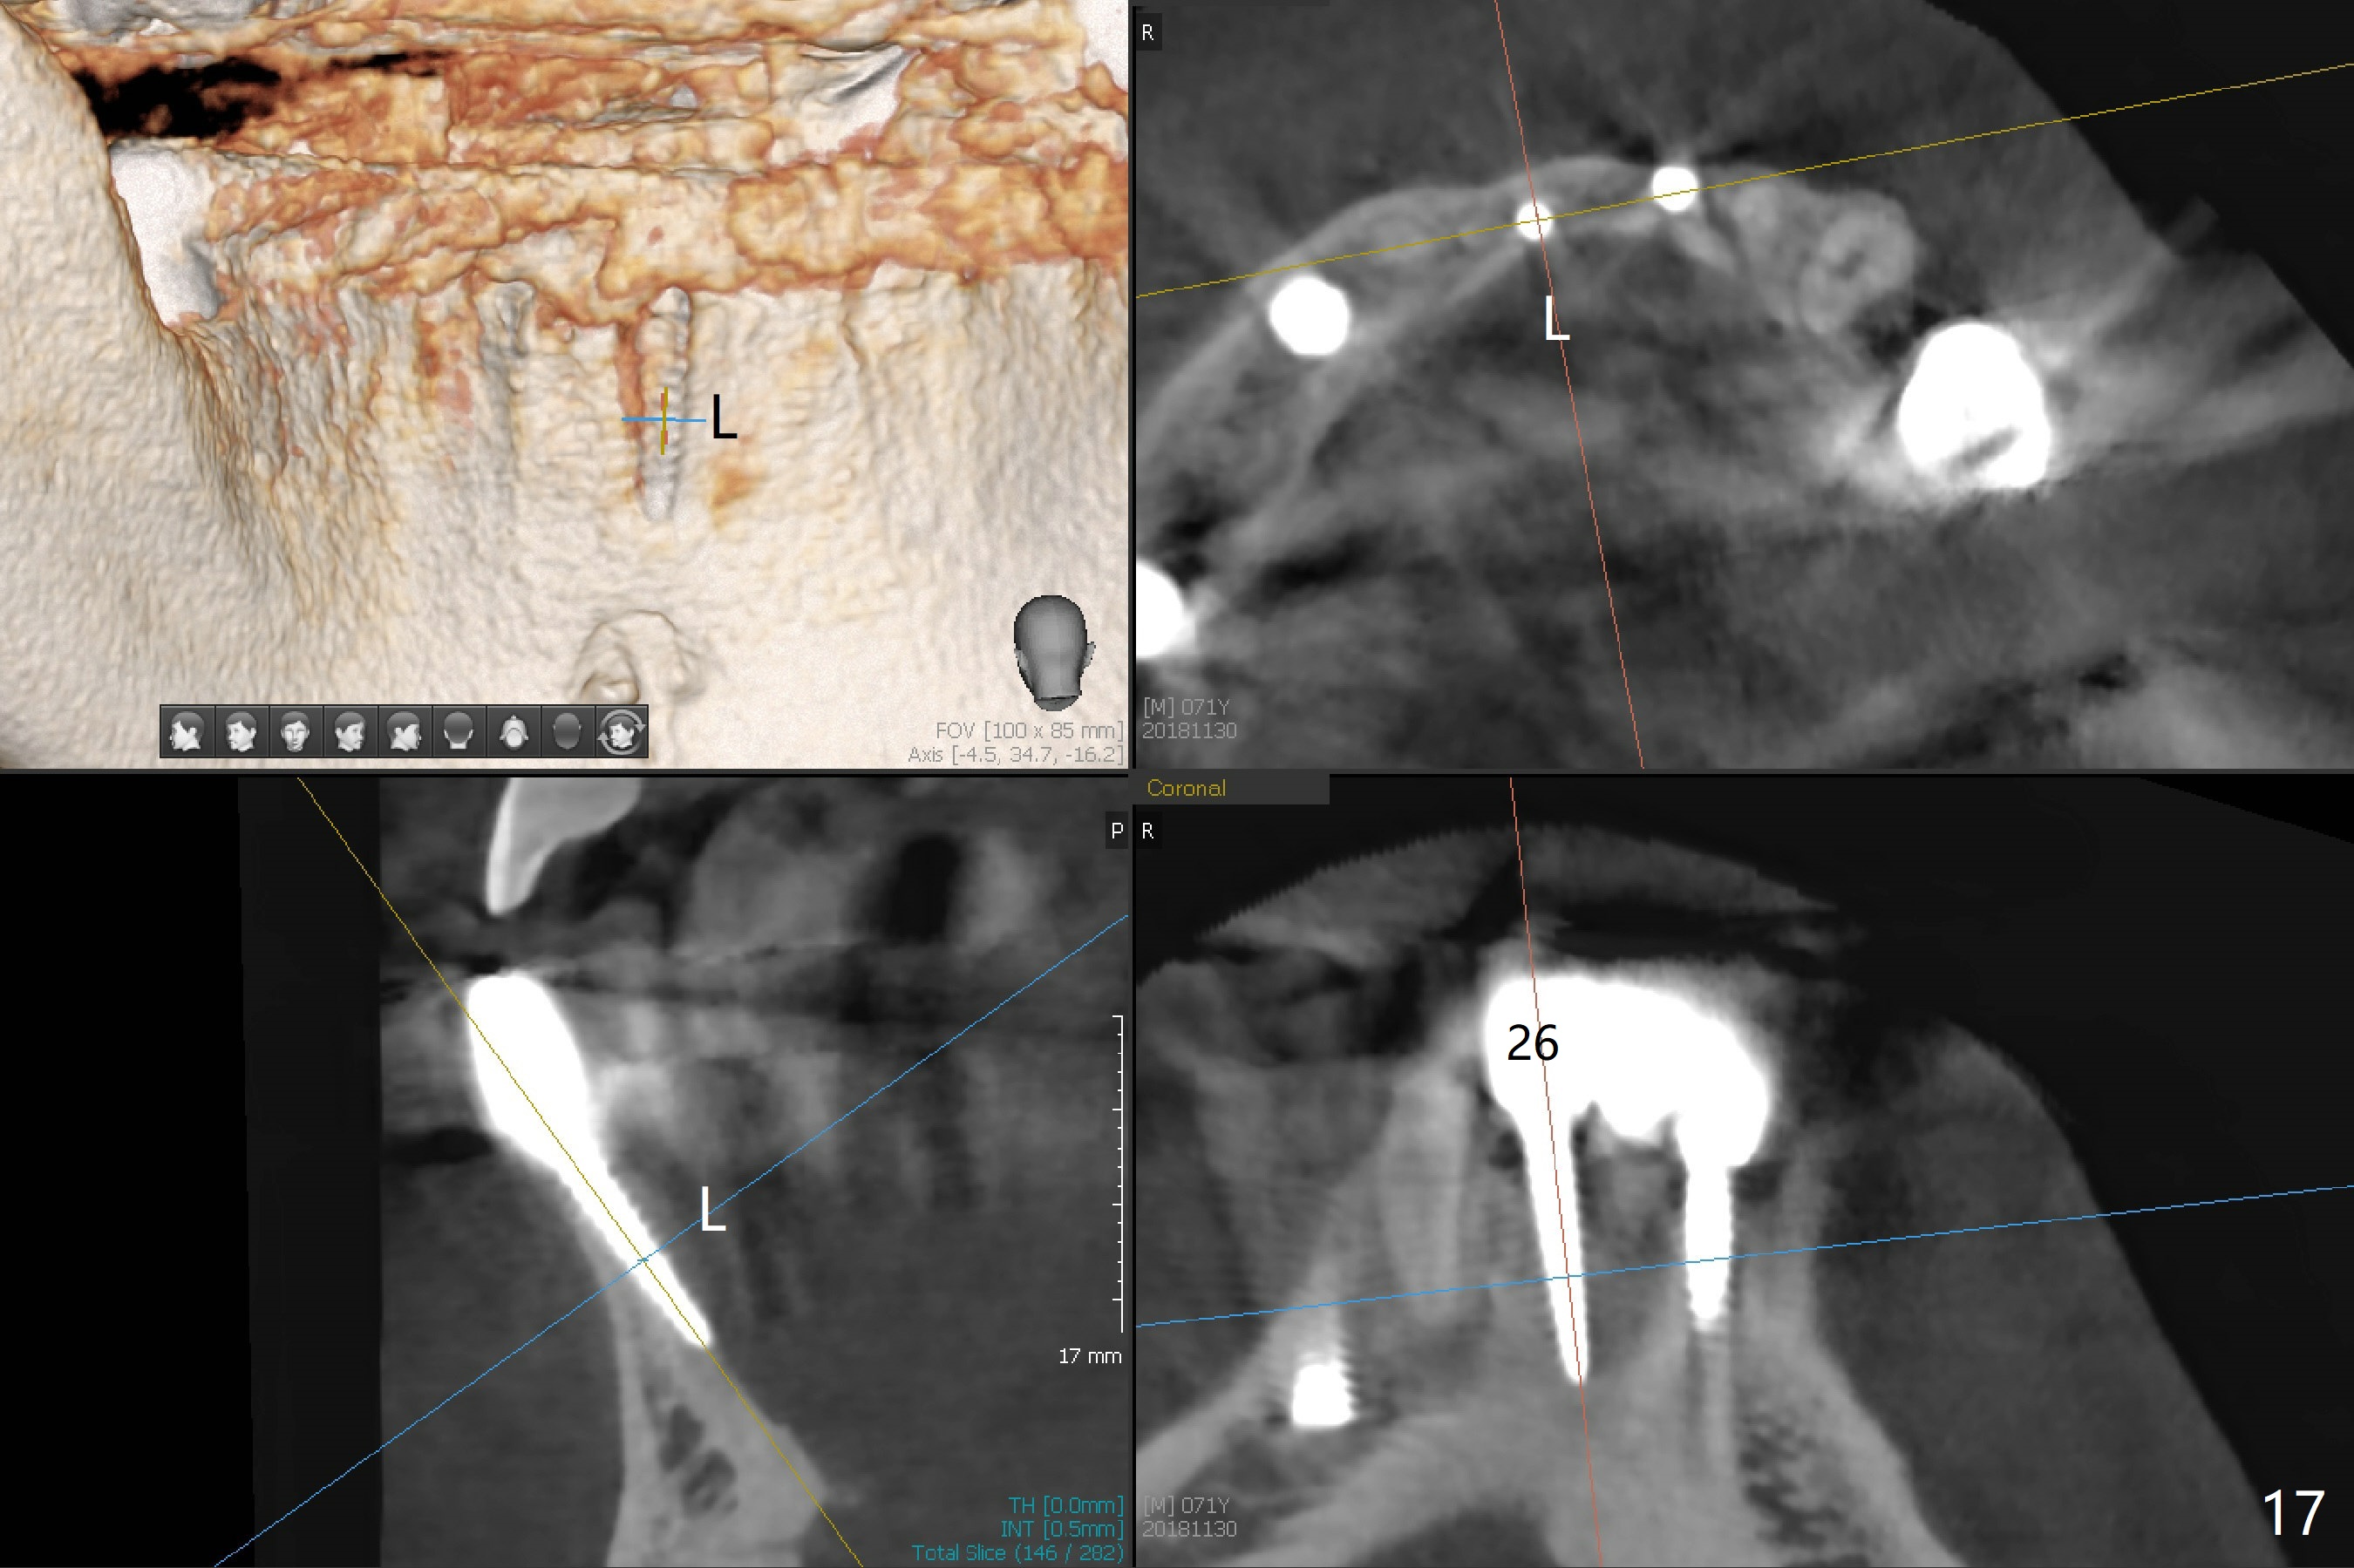

Fig.7 shows these two one piece implants immediately prior to cementation of the FPD (Fig.8). They are much more parallel to each other after prep, as compared to Fig.6. Fig.9 shows apparent bone growth around #24 implant (at the crest) 6,9 months post cementation and surgery, respectively. Orthodontic treatment will incorporate the fixed partial denture. Fig.10 shows that bone grows coronally (arrow) to cover 3 threads (from #6 thread to #3) at the site of #24 one year after functioning. There is mild buccal gingival infection involving #26 retainer. Preop CBCT is reviewed to determine whether it is related to potential thread exposure. It appears that at the sites of #24 (Fig.13,14) and 26 (Fig.11,12), 2.5 mm implant is more appropriate for the narrow ridge than 3.0 mm one. In fact, periimplantitis develops at #26 two years of absence of perio maintenance (because of atrial fibrillation with blood thinner; Fig.15, 3 years 7 months post cementation). Periimplantitis persists 4.5 months later. Although water pik is purchased, it is not used often because of low blowing force. If needed, remove the FPD atraumatically. Unwind the implant, clean the coronal threads with Titanium brush or remove the exposed threads and replant the implant with bone graft.

The infection persists at #26 four years 8 months post cementation (Fig.16 *). CBCT is taken. In fact the implant at #26 was placed lingual (Fig.17), while that at #24 buccal (Fig.20). The 2nd option is to remove the implant at #26 and place a 2 mm one at #25 (Fig.18,19). Fabricate a 3-unit cantilever FPD. Take 5x5 cm CT with 1.2 mm drill in place for 10 mm. Change the trajectory and position if necessary.